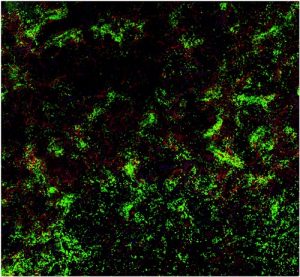

Bluterkrankheit: Das Immunsystem zur Toleranz erziehen1. November 2022 Gewebeprobe aus der Milz einer Maus: Die B-Zellen (grün) interagieren mit Faktor VIII (rot). (Foto: © AG Becker-Gotot/Universitätsklinikum Bonn) Die Hämophilie A ist die häufigste schwere Form der Bluterkrankheit und lässt sich in der Regel gut behandeln – allerdings nicht bei allen Betroffenen. Eine Studie an der Universität Bonn hat nun einen wichtigen Mechanismus aufgeklärt, der für die Wirkung der Therapie entscheidend ist. Bei Hämophilie-A-Betroffenen ist ein Protein defekt, das für die Blutgerinnung wichtig ist: der Faktor VIII. Zur Behandlung erhalten die meisten Betroffenen daher alle paar Tage eine intravenöse Injektion mit dem funktionsfähigen Gerinnungsfaktor. Doch häufig und besonders zu Beginn der Behandlung erkennt das Immunsystem den gespritzten Wirkstoff als körperfremd und attackiert ihn. Dies ist die schwerste Komplikation der Hämophilie-Behandlung, weil Faktor VIII dann nicht mehr wirken kann. In diesen Fällen hilft oft eine Immuntoleranz-Therapie, die bereits vor mehr als 40 Jahren ebenfalls am Universitätsklinikum Bonn (UKB) entwickelt wurde. Dabei wird den Bluterkranken über mehrere Monate regelmäßig eine hohe Dosis Faktor VIII gespritzt. Das Immunsystem gewöhnt sich dadurch an das injizierte Protein und toleriert es. „Allerdings klappt das nicht immer“, erklärt Prof. Johannes Oldenburg, Direktor des Instituts für Experimentelle Hämatologie und Transfusionsmedizin des UKB. „Bei etwa 30 Prozent der Patienten führt die Gewöhnung nicht zum Erfolg. Ihre körpereigene Abwehr attackiert also weiterhin das Faktor-VIII-Protein und vernichtet es, sodass Faktor VIII nicht zur Behandlung eingesetzt werden kann. Wir wollten wissen, woran das liegt.“ Dazu hat sich das Team zwei Zelltypen des Immunsystems angesehen, die B-Zellen und die regulatorischen T-Zellen. Bremse im Immunsystem Regulatorische T-Zellen verhindern, dass eine Immunreaktion zu stark ausfällt oder zu lange anhält. Die Forschenden haben unter ihnen nun eine neue Art gefunden, die speziell gegen bestimmte B-Zellen vorgehen kann und nicht nur unspezifisch gegen alle Immunantworten. „Wir konnten zeigen, dass die Immuntoleranz-Therapie zur Bildung regulatorischer T-Zellen führt, die ausschließlich B-Zellen gegen Faktor VIII zum Selbstmord veranlassen“, sagt Dr. Janine Becker-Gotot vom Institut für Molekulare Medizin und Experimentelle Immunologie (IMMEI) des UKB. „Diese T-Zellen verfügen über einen Sensor, mit dem sie die entsprechenden B-Zellen erkennen und sich an sie heften. Zusätzlich haben sie die Fähigkeit, den Selbstzerstör-Knopf auf der Oberfläche der B-Zellen zu drücken.“ Dieser Knopf ist ein Molekül namens PD-1. Durch seine Aktivierung startet er in der B-Zelle ein Programm, das zu ihrem Tod führt. Jede aktive B-Zelle verfügt über diesen Knopf. „Wir konnten in unseren Experimenten erstmals regulatorische T-Zellen nachweisen, die diesen Selbstzerstör-Knopf nur bei ganz bestimmten B-Zellen aktivieren können, um ungewollte Immunantworten gezielt zu verhindern“, erklärt der Direktor des IMMEI, Prof. Christian Kurts. Je mehr PD-1-Knöpfe die B-Zellen gegen Faktor VIII auf ihrer Oberfläche tragen, desto leichter lassen sie sich durch die Immuntoleranz-Therapie in den Selbstmord treiben. „Die PD-1-Menge ist von Person zu Person verschieden“, erklärt Becker-Gotot. „Ist sie von vornherein sehr gering, ist die Wahrscheinlichkeit groß, dass viele Hemmkörper-produzierende B-Zellen überleben und den injizierten Faktor VIII weiterhin neutralisieren.“ Test soll zeigen, bei wem eine Immuntoleranz-Therapie sinnvoll ist Interessanterweise bilden B-Zellen auch mehr PD-1, sobald sie mit regulatorischen T-Zellen in Kontakt kommen. „Wir können inzwischen testen, wie stark diese Reaktion ausfällt“, sagt die Wissenschaftlerin. „Wenn die PD-1-Menge kurz nach Start der Immuntoleranz-Therapie hoch geht und dann auch oben bleibt, ist das ein klares Zeichen dafür, dass sie Erfolg haben wird.“ Das Team entwickelt gerade einen Bluttest, mit dem sich schon während der langwierigen Behandlung erkennen lässt, ob bei den Betroffenen die Immuntoleranz-Therapie anschlägt oder nicht. „Unsere Erkenntnisse haben großen grundlagenwissenschaftlichen Wert“, erklärt Kurts, der an der Universität Bonn dem Transdisziplinären Forschungsbereich „Life & Health“ angehört sowie – wie auch Becker-Gotot und Oldenburg – Mitglied im Exzellenzcluster ImmunoSensation ist. „Und zwar nicht nur für die Hämophilie, sondern auch für andere angeborene Erkrankungen, bei denen fehlende Proteine therapeutisch ersetzt werden. Langfristig könnten sie sich auch zur Entwicklung neuer Behandlungsmethoden nutzen lassen.“ Beteiligte Institutionen und Förderung: An der Studie waren neben dem IMMEI und dem Institut für Experimentelle Hämatologie und Transfusionsmedizin am Universitätsklinikum Bonn die IMC University of Applied Sciences im österreichischen Krems und die University of Melbourne (Australien) beteiligt. Die Arbeiten wurden durch die Deutsche Forschungsgemeinschaft (DFG), das Universitätsklinikum Bonn (Bonfor), ein gemeinsames Graduiertenkolleg der Universitäten Bonn und Melbourne, die Studienstiftung des Deutschen Volkes sowie die europäische „innovative medicine innitiative“ (IMI) gefördert.